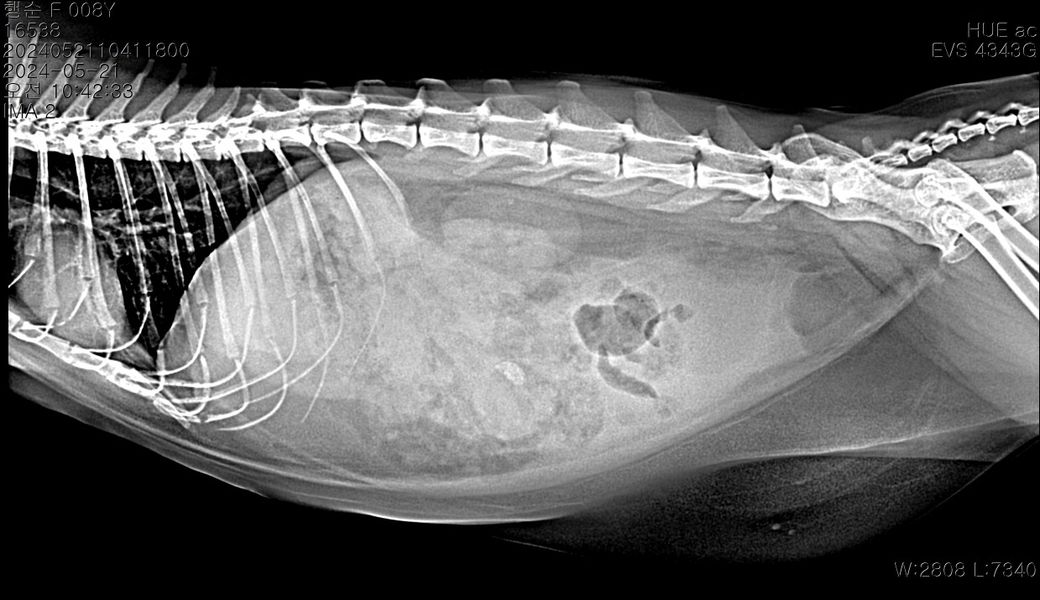

중등도 이상의 복수가 있는 상태이며 8세령이라면 복수의 원인으로 장파열에 의한 세균 감염성 복막염, 림프종과 같은 종양성 질환, 심장 질환, 대사성 질환, 고양이 전염성 복막염 등 다양한 원인을 고려해야 합니다. 복수에 대한 복수 검사를 기본으로 전신적인 종합검사가 필요합니다.